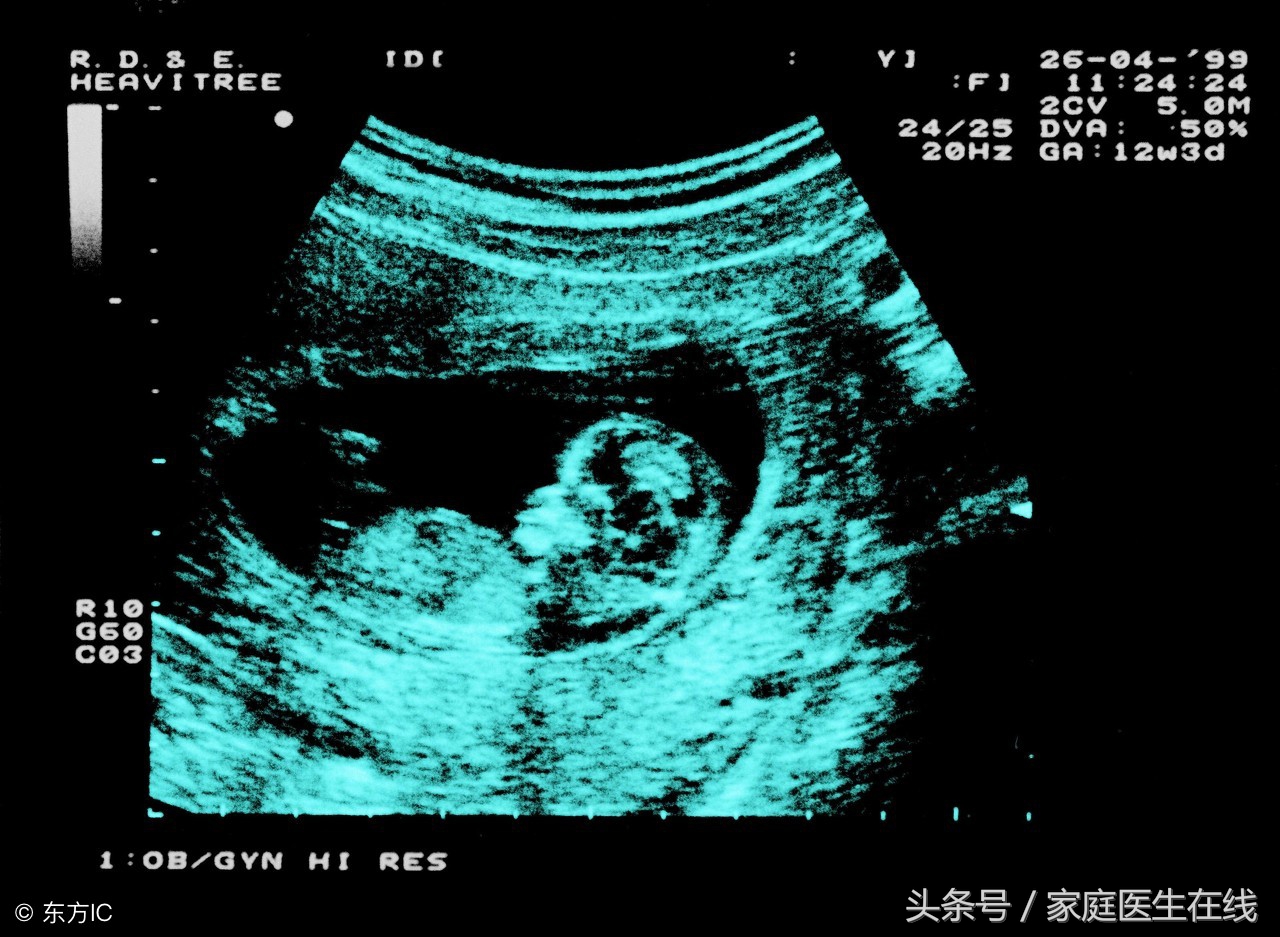

每一位妈妈怀孕以后,都希望能够早一点见到自己心爱的宝宝,想知道宝宝长的什么样子、是个男宝还是女宝。有人说,从胎心监护图可以看出小宝宝的性别。那么,胎心监护图看男女靠谱吗?在下将为大家解答。

一、胎心监护图不能看男女很多准爸爸和妈妈都喜欢通过胎心监护来猜测胎儿的性别,但其实这完全没有任何科学依据。

医生介绍说,胎心监护并不能看出肚子里的宝宝是男孩还是女孩,而只能监测胎儿的健康状况。一般主要包括检查胎儿是否缺氧、胎儿心跳的跳动频率是否正常等,但并不能根据胎儿的心跳基线来分辨出胎儿的性别。